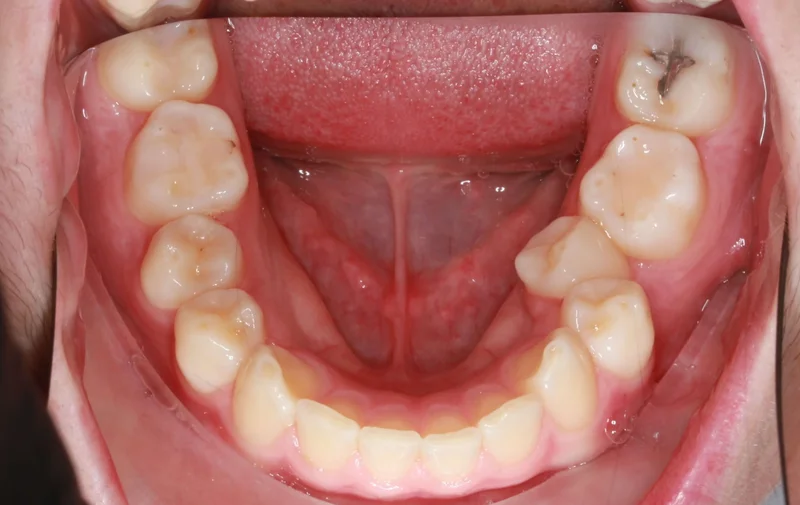

Lower Arch

Lower Arch - Before Treatment

Before

Lower Arch - After Treatment

After